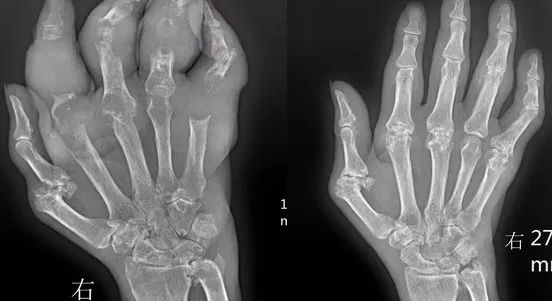

误区三:尿酸水平正常后,只用饮食控制就行了?

当尿酸水平达到目标范围后立即停药,尿酸代谢和排泄会逐步恢复原态,这是因为患者只是将血液中的尿酸降下来了,而皮下、肌肉、关节等各处沉积的尿酸盐结晶依然存在,这部分尿酸盐结晶又会溶解进血液中,使血尿酸水平回升。并且仅通过饮食控制只能减少外源性嘌呤摄入,不能改善肾脏对尿酸的排泄和内源性尿酸的生成。当尿酸水平达到目标值后,需要在专业医生的指导下,逐步减少降尿酸药物剂量,直到用最小剂量也能控制住血尿酸值在目标范围,长期维持一段时间后,再在医生的指导下尝试停药。如果患者有其他情况,如严重痛风石、高血压等,可能需要长期用药。